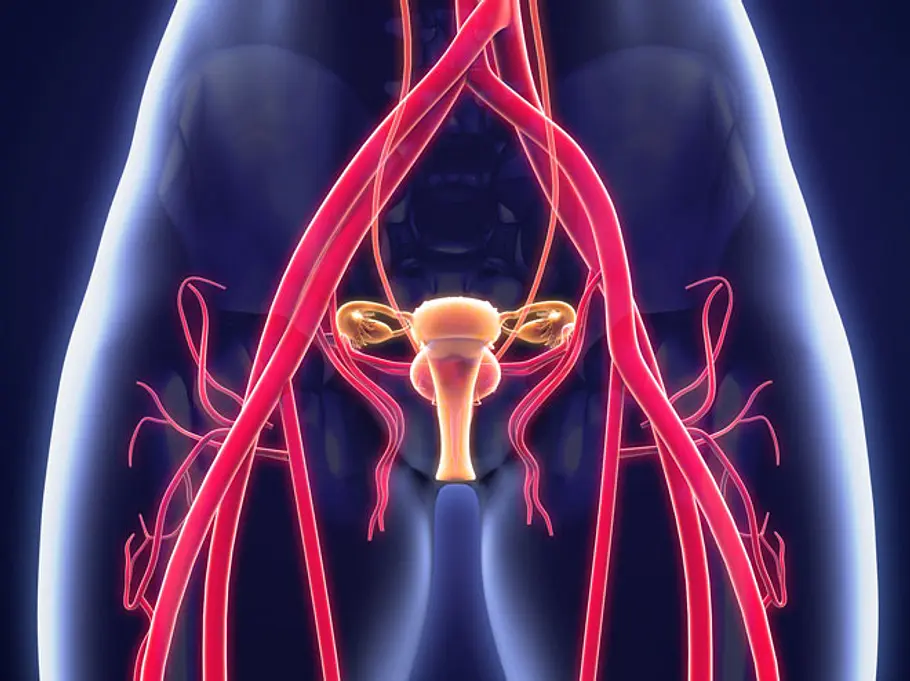

Zwei Vaginen? Wie darf man sich das vorstellen? Für Nicci bedeutet es konkret, dass sie zwar nur eine Vaginalöffnung hat und auch ihre Schamlippen ganz normal aussehen. Im Inneren ihres Körpers jedoch teilt sich der Vaginakanal in zwei separate Öffnungen. Es sind zwei Gebärmutterhälse vorhanden. Außerdem befindet sich auf beiden Seiten ein Uterus.

Noch etwas belastete Nicci sehr: ihr Wunsch, ein Baby zu bekommen. Drei Fehlgeburten musste sie ertragen. Nach ihrer letzten kam es zu der sechs Monate andauernden Blutung. Das Problem: Der Platz in Niccis Körper, der normalerweise für einen Uterus gedacht ist, wurde von zwei einzelnen Gebärmüttern genutzt.